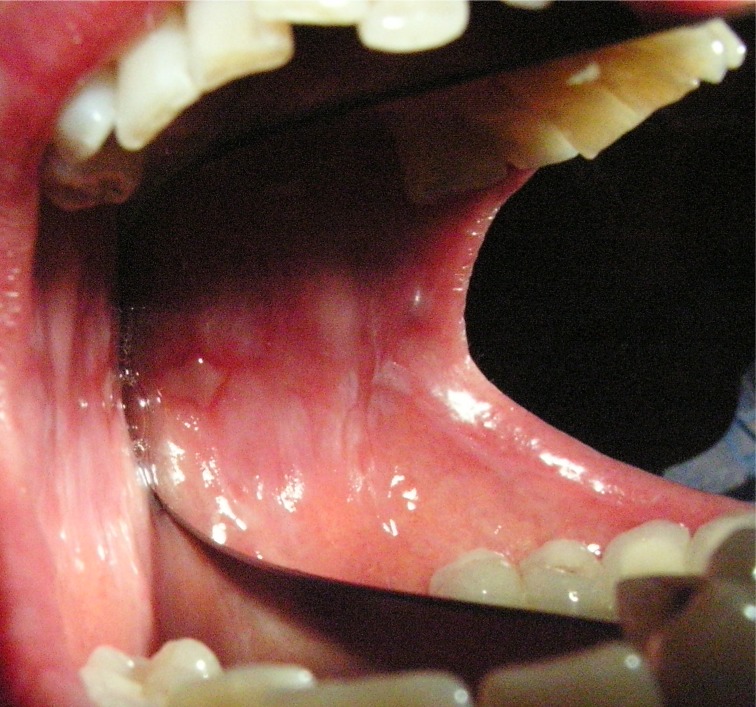

Cara Signora Martina, il cortisone va usato con molta prudenza e soprattutto deve essere sospeso a "scalare", a fine cura! Però lo si deve usare solo come "terapia" d'urto nella fase acuta e solo dopo aver fatto una reale e sicura Diagnosi Clinica confermata da Diagnosi Isto-patologica. Quello che lei descrive non è la sintomatologia di una semplice e generica Gengivite, ma di qualche altra patologia, sempre gengivale o mucogengivale in cui bisogna porre una Diagnosi Differenziale certa tra Gengivite Desquamativa, Ulcero-necrotica, pemfigoide, bollosa e tante altre. A tutte si può accompagnare o sovrapporre un lichen planus del cavo orale (OLP). Esistono 4 varianti di OLP: reticolare, atrofico, erosivo-bolloso e a placca. La forma erosiva e quella bollosa, evoluzione probabilmente di una forma nell’altra, rappresentano le varianti più sintomatiche e che più spesso si accompagnano o sovrappongono a Gengiviti particolari come quelle descritte, con una compromissione notevole della qualità di vita. Nella diagnostica differenziale di queste forme rientrano i tumori, la stomatite cronica erosiva, il lupus eritematodes, l’eritema polimorfo, le candidiasi, le reazioni da farmaci. La onde ragion per cui, consiglio uno o più prelievi bioptici ed una diagnosi anche ist-patologica per valutare soprattutto se esistono note di acantosi, ipercheratosi, ipergranulosi, degenerazioni varie etc e porre così una diagnosi certa istologica senza cui si andrebbe avanti solo per tentativi! Attenzione al Cortisone! E' ovvio che possa calmare temporaneamente i sintomi ma il suo uso, ripeto deve avvenire solo se è stata fatta una Diagnosi Differenziale Certa perchè in alcune di queste patologie può essere addirittura controindicato ed aggravare la patologia! Giudicherà il suo Dentista se inviarla da un Dentista Esperto in Patologia Orale!Le lascio una foto di un mio caso Clinico proprio di pochi mesi fa!Cordialmente Gustavo Petti, Parodontologia, Implantologia, Gnatologia e Riabilitazione Orale Completa in Casi Clinici Complessi ed Ortodonzia e Pedodonzia la figlia Claudia Petti, in Cagliari